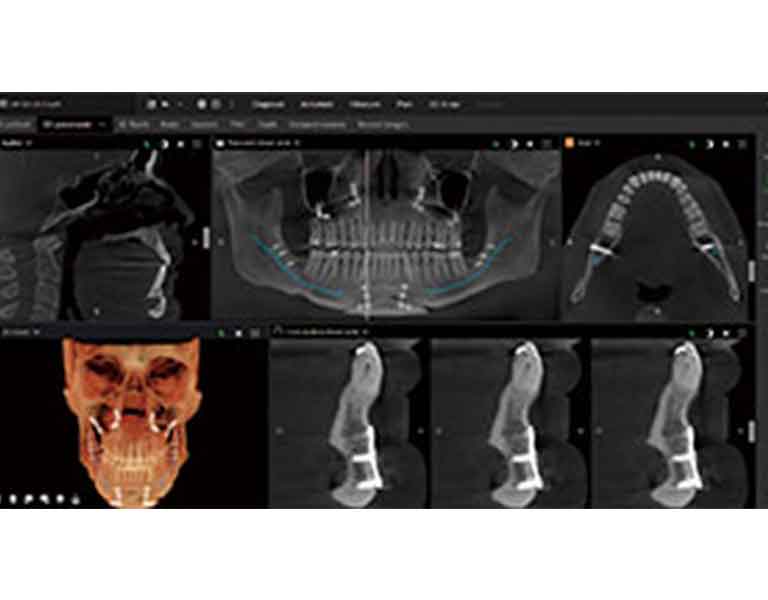

様々な場面での高解像度スキャンを実現

インプラント、歯科矯正、根管治療(根の治療)、親知らずの診断、歯周病治療など、それぞれの治療内容に最適な高解像度スキャンが可能になり、正確で迅速な診査・診断、適切な治療計画を立てることができます。

最適なポジショニングが可能

撮影の際のポジショニング(位置付け)はパノラマ画像(お口全体のレントゲン)の画像の質に大きく関係し、位置付けが悪いと情報が読み取りにくくなってしまい、再撮影が必要になります。

DEXIS オルソパントモグラフ OP 3D LXでは、ポジショニングが簡単に、正確に行えますので、均一な画質のパノラマ画像が得られます。

金属のアーチファクトを低減

次世代の画像向上テクノロジーにより、インプラント内部構造を見ることができ、金属によるアーチファクト(画像の乱れ)の影響を最小限に抑え、診断の精度が高まります。